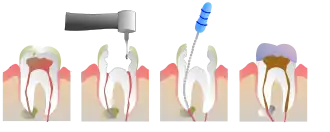

Наиболее частыми причинами повреждения или отмирания пульпы являются наличие трещины, либо глубокой кариозной полости в зубе[4]. В стоматологической практике в процессе эндодонтического лечения острого гнойного и хронического пульпита производится механическая и медикаментозная обработка системы корневых каналов зуба (депульпирование — удаление сосудов и нерва) с последующей пломбировкой (герметичной обтурацией) канала(ов). Данный вид лечения исполняется в двух вариантах:

- девитальная экстирпация — удаление сосудисто-нервного пучка проводится за 2 посещения. При первом создаётся сообщение с пульпарной камерой зуба, в которую накладывают девитализирующую пасту (так называемый «мышьяк», который уже практически не используется и заменён менее токсичной пастой на основе параформальдегида и анестетика).

- витальная экстирпация — при отсутствии выраженных воспалительных явлений, переходящих в периодонт, удаление сосудисто-нервного пучка и его обтурация проводится под анестезией в одно посещение. В канале оставляют лекарство (для антисептики и снятия воспаления). В процессе лечения необходимо сделать как минимум 2 рентгеновских снимка: первый — до начала лечения (для оценки длины и структуры каналов), а второй — после (для оценки качества пломбирования каналов).